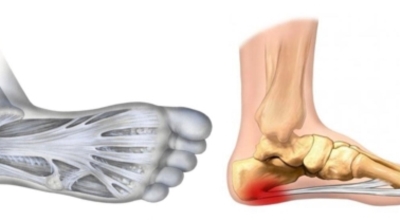

족저 근막이란 발가락 시작지점부터 발뒤꿈치뼈까지 발바닥 전체를 감싸고 있는 두꺼운 막을 말해요. 족저 근막은 발바닥 아치를 지속시켜 발바닥이 지면을 내딛음으로써 나타나는 충격을 흡수하는 중요한 역할을 수행하고 있어요. 이 족저 근막에 일차적으로 서서히 조직 손상이 일어나고 계속적인 활동으로 인해 염증이 커지면서 발 뒤꿈치 부근 통증을 유발하게 되는데 염증은 무리하고 반복적인 동작, 과도한 사용으로 마찰에 의해 발생해요.

주요 증상은 통증으로 발뒤꿈치 안쪽이 아주 아프며, 맨발로 바닥을 걸을 때 걸음을 내딛을 때마다 통증이 있어요. 가장 심한 통증은 아침에 일어나 첫 걸음을 뗄 때인데, 밤에 족저근막이 수축하다가 발에 체중이 가해지면서 갑자기 늘어나는 현상입니다.

운동할 때는 괜찮은데 운동하고 나면 간혹 아플 때가 있습니다. 심한 경우 보행에 영향을 준다고 합니다. 이 질병을 예방하려면 오랫동안 서 있거나 딱딱한 바닥에 발을 올려놓는 것을 피해야 해요. 신발 선택도 중요해요. 꽉 끼는 신발, 무거운 신발, 하이힐, 딱딱한 신발 또는 높은 깔창을 피하고 쿠션이 강화된 가벼운 신발을 착용하십시오.